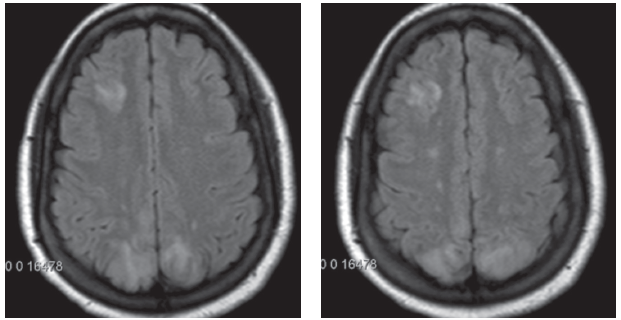

A plain head CT and electroencephalography were unremarkable. A brain MRI revealed increased T2/fluid attenuated inversion recovery (FLAIR) intensities in the right frontal, bilateral parietal, and occipital subcortical white matter and cortex consistent with posterior reversible encephalopathy syndrome (PRES).

Figures 1 and 2. Brain MRI in axial view showing the increased T2/FLAIR intensities in the right frontal, bilateral parietal, and occipital subcortical white matter and cortex, suggestive of symmetrical edema.